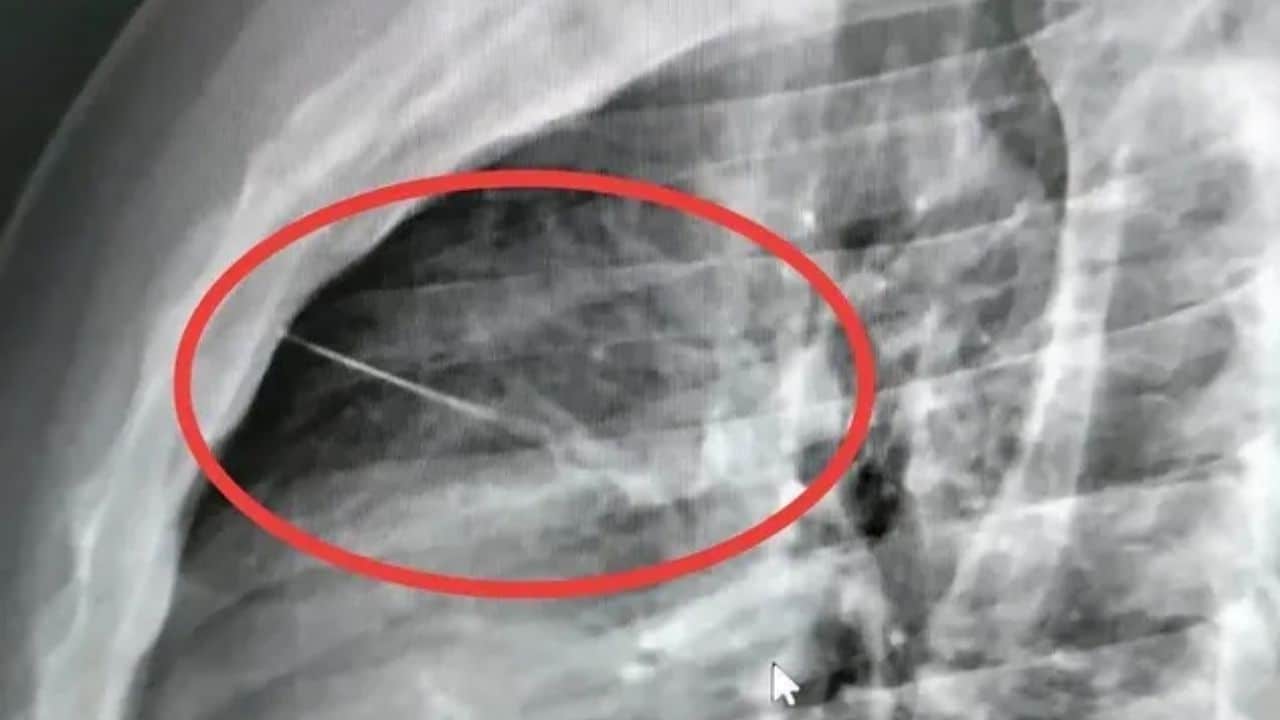

Мужчина из тайской провинции Бурирам находится в критическом состоянии после того, как врачи обнаружили семисантиметровую иглу в его груди рядом с сердцем. Вчера, 24 марта, спасатели были вызваны в дом в районе Красанг, чтобы помочь Бунлерту Саттараму, который сообщил о боли в груди. Сообщается, что он пытался пить воду, чтобы облегчить симптомы, …